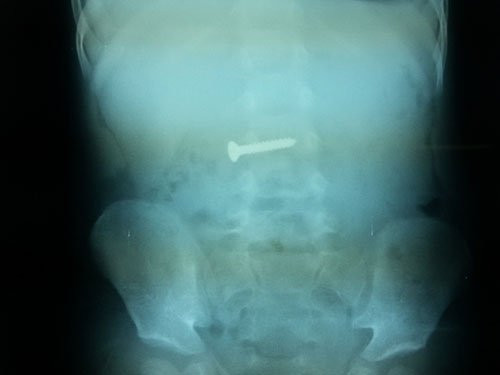

Tại bệnh viện, qua thăm khám, chụp X–quang, các bác sĩ phát hiện 1 dị vật cản quang trong dạ dày bệnh nhi. Bệnh viện tiến hành hội chẩn và quyết định nội soi gây mê để lấy dị vật ra khỏi cơ thể cháu bé.

Bác sĩ Phùng Thị Hằng cho biết: "Sau khi đặt máy chúng tôi xác định dị vật xuống sâu hơn ở D3 tá tràng so với phim X-quang. Do dị vật có bề mặt xoắn ốc lại dài 3cm so với kích thước lồng ruột của trẻ 2 tuổi nên thủ thuật tiến hành rất khó khăn.

Tuy nhiên, sau khoảng 30 phút phối hợp dị vật được lấy ra khỏi cơ thể cháu bé một cách ngoạn mục. Kết quả kiểm tra lại cho thấy, niêm mạc tá tràng, dạ dày, thực quản của cháu bé không tổn thương, không chảy máu".